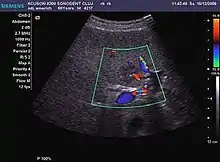

US examination is required to detect liver metastases in patients with oncologic history. In addition, the method can incidentally detect metastases in asymptomatic patients. Early identification (small sizes, small number) is important to establish an optimal course of treatment which can be complex (chemotherapy, radiofrequency ablation, surgical resection) but welcomed. In addition, discrimination of synchronous lesions that have a different nature is also important knowing that up to 25–50% of liver lesions less than 2 cm detected in cancer patients may be benign . US sensitivity for metastases detection varies depending on the examiner's experience and the equipment used and ranges between 40 and 80% . Sensitivity is conditioned by the size and acoustic impedance of the nodules. For a lesion diameter below 10 mm US accuracy is greatly reduced, reaching approx. 20%. Other elements contributing to lower US performance are: excessive obesity, fatty liver disease, hypomobility of the diaphragm, and certain patterns of hyperechoic or isoechoic metastases that can be overlooked or can mimic benign conditions. Conventional US appearance of metastases is uncharacteristic, consisting of circumscribed lesions, with clear, imprecise or "halo" delineation, with homogeneous or heterogeneous echo pattern. They can be single (often liver metastases from colonic neoplasm) or multiple. Echogenity is variable. When increased, they can compress the bile ducts (which may be dilated) and the liver vessels. Liver involvement can be segmental, lobar or generalized. In this situation a pronounced hepatomegaly occurs. Generally, metastases have non-characteristic Doppler vascular pattern, with few exceptions (carcinoid metastases). Cyst-adenocarcinoma metastases due to semifluid content may have a transonic appearance. When increasing, they can result in central necrosis. CEUS examination is a real breakthrough for detection and characterization of liver metastases.

Increased performance is based on identifying specific vascular patterns during the arterial phase and seeing metastases in contrast to normal liver parenchyma during the sinusoidal phase. CEUS increased accuracy is due to the different behavior of normal liver parenchyma (captures CA in Kuppfer cells) against tumor parenchyma (does not contain Kuppfer cells, therefore CEUS appearance is hypoechoic). To this adds the particularities of intratumoral circulation represented by a reduced arterial bed compared to that of the surrounding normal liver and the absence of the portal vessels . In terms of vascularity, metastases can be hypovascular (in gastric, colonic, pancreatic or ovarian adenocarcinomas) with hypoechoic pattern during arterial phase, and similar during portal venous and late phases, respectively hypervascular (neuroendocrine tumors, malignant melanoma, sarcomas, renal, breast or thyroid tumors) with hyperechoic appearance during arterial phase, with washout during the portal venous phase and hypoechoic pattern 30 seconds after injection.